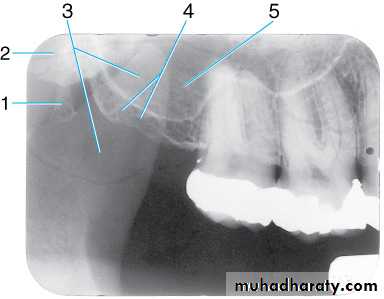

Radiograph of maxillary molar area. This radiograph shows (1) border (floor) of maxillary sinus, (2) maxillary sinus, (3) zygomatic process of maxilla, (4) zygoma, (5) lateral pterygoid plate, (6) lower border of zygomatic arch, (7) maxillary tuberosity, and (8) coronoid process of the mandible

Radiograph of maxillary molar area. This radiograph shows (1) hamulus (hamular process), which is a downward projection of the medial pterygoid plate, (2) lateral pterygoid plate, (3) coronoid process of the mandible, (4) maxillary tuberosity, and (5) maxillary sinus